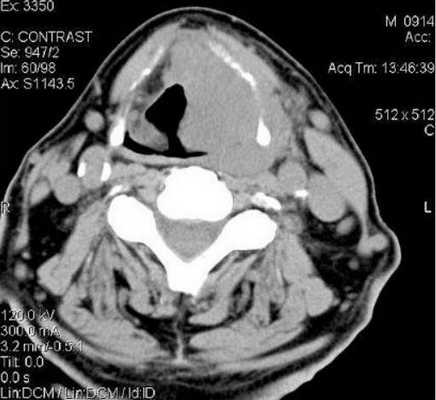

КТ щитовидной железы с контрастом

КТ тканей щитовидной железы требует контрастирования, поскольку обычные изображения не показывают узелки, сосуды, опухоли. С целью улучшения визуализации внутривенно вводят специальные йодсодержащие препараты. Попадая в кровеносное русло, контрастирующее средство быстро заполняет сосудистую сеть органа и четко выделяет на томограммах не только последнюю, но и патологически измененные участки.

Фото КТ щитовидной железы с контрастом